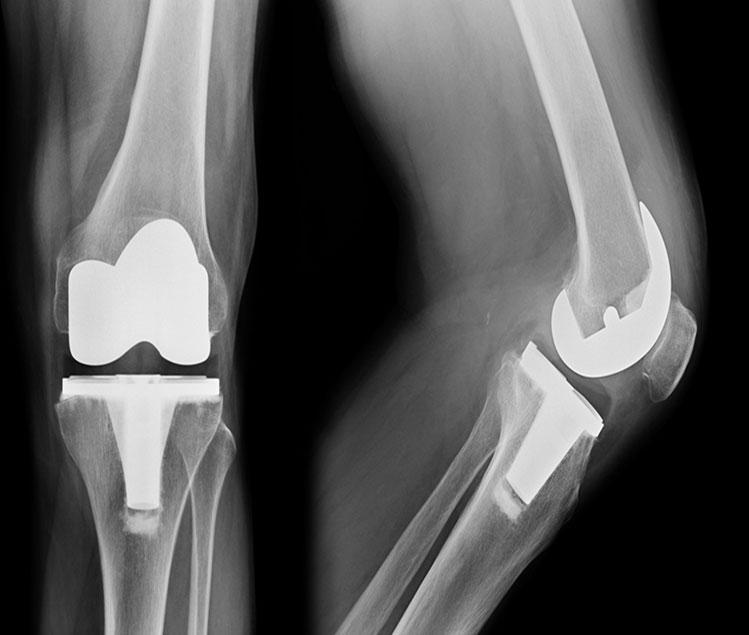

Revision Knee & Hip Replacement

Total Knee Joint Replacement (TKR) revision surgery is an orthopaedic surgical procedure in which the prosthetic pieces(s) of the previous TKR surgery are removed. New prosthetic pieces are then replaced within the knee joint. The components consist of the femoral condyle component, the tibial plateau component, the polyethylene spacer and the patella component. All or some of these may be replaced depending on the reason for replacement.

Revisional TKR surgery is a more complicated operation requiring longer time in theater and rehabilitation is slower and takes a more cautious approach.